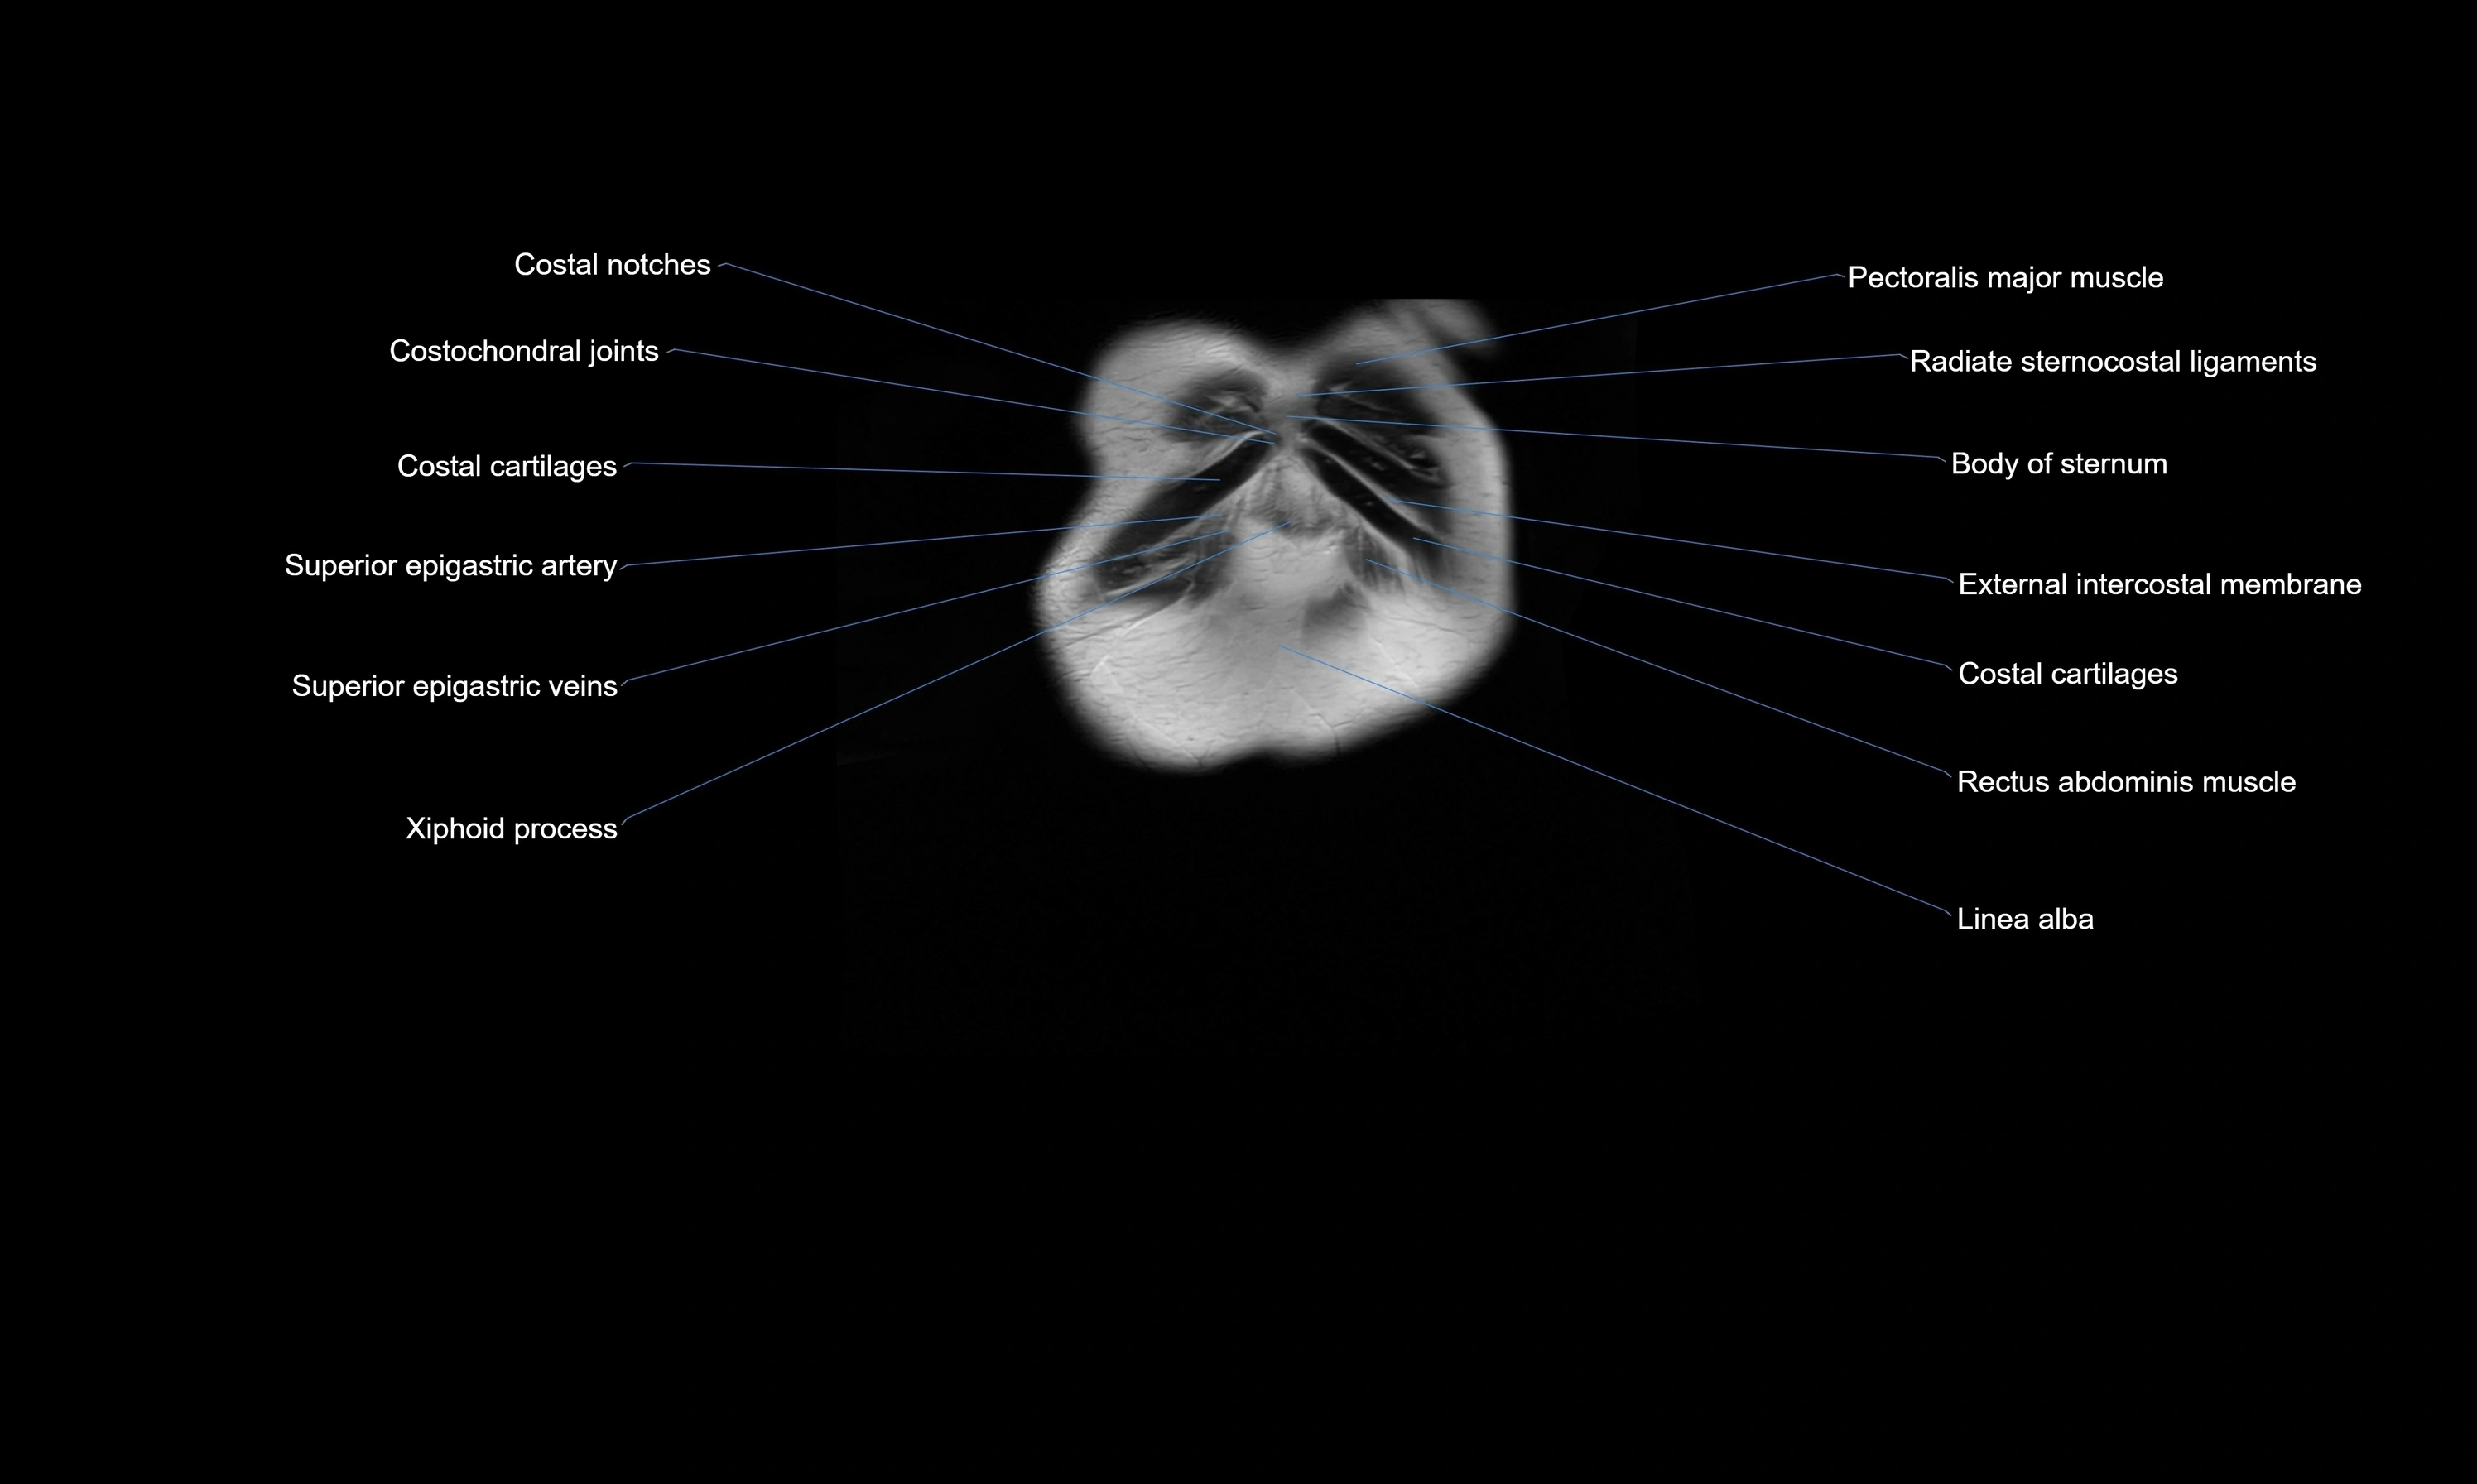

MRI images